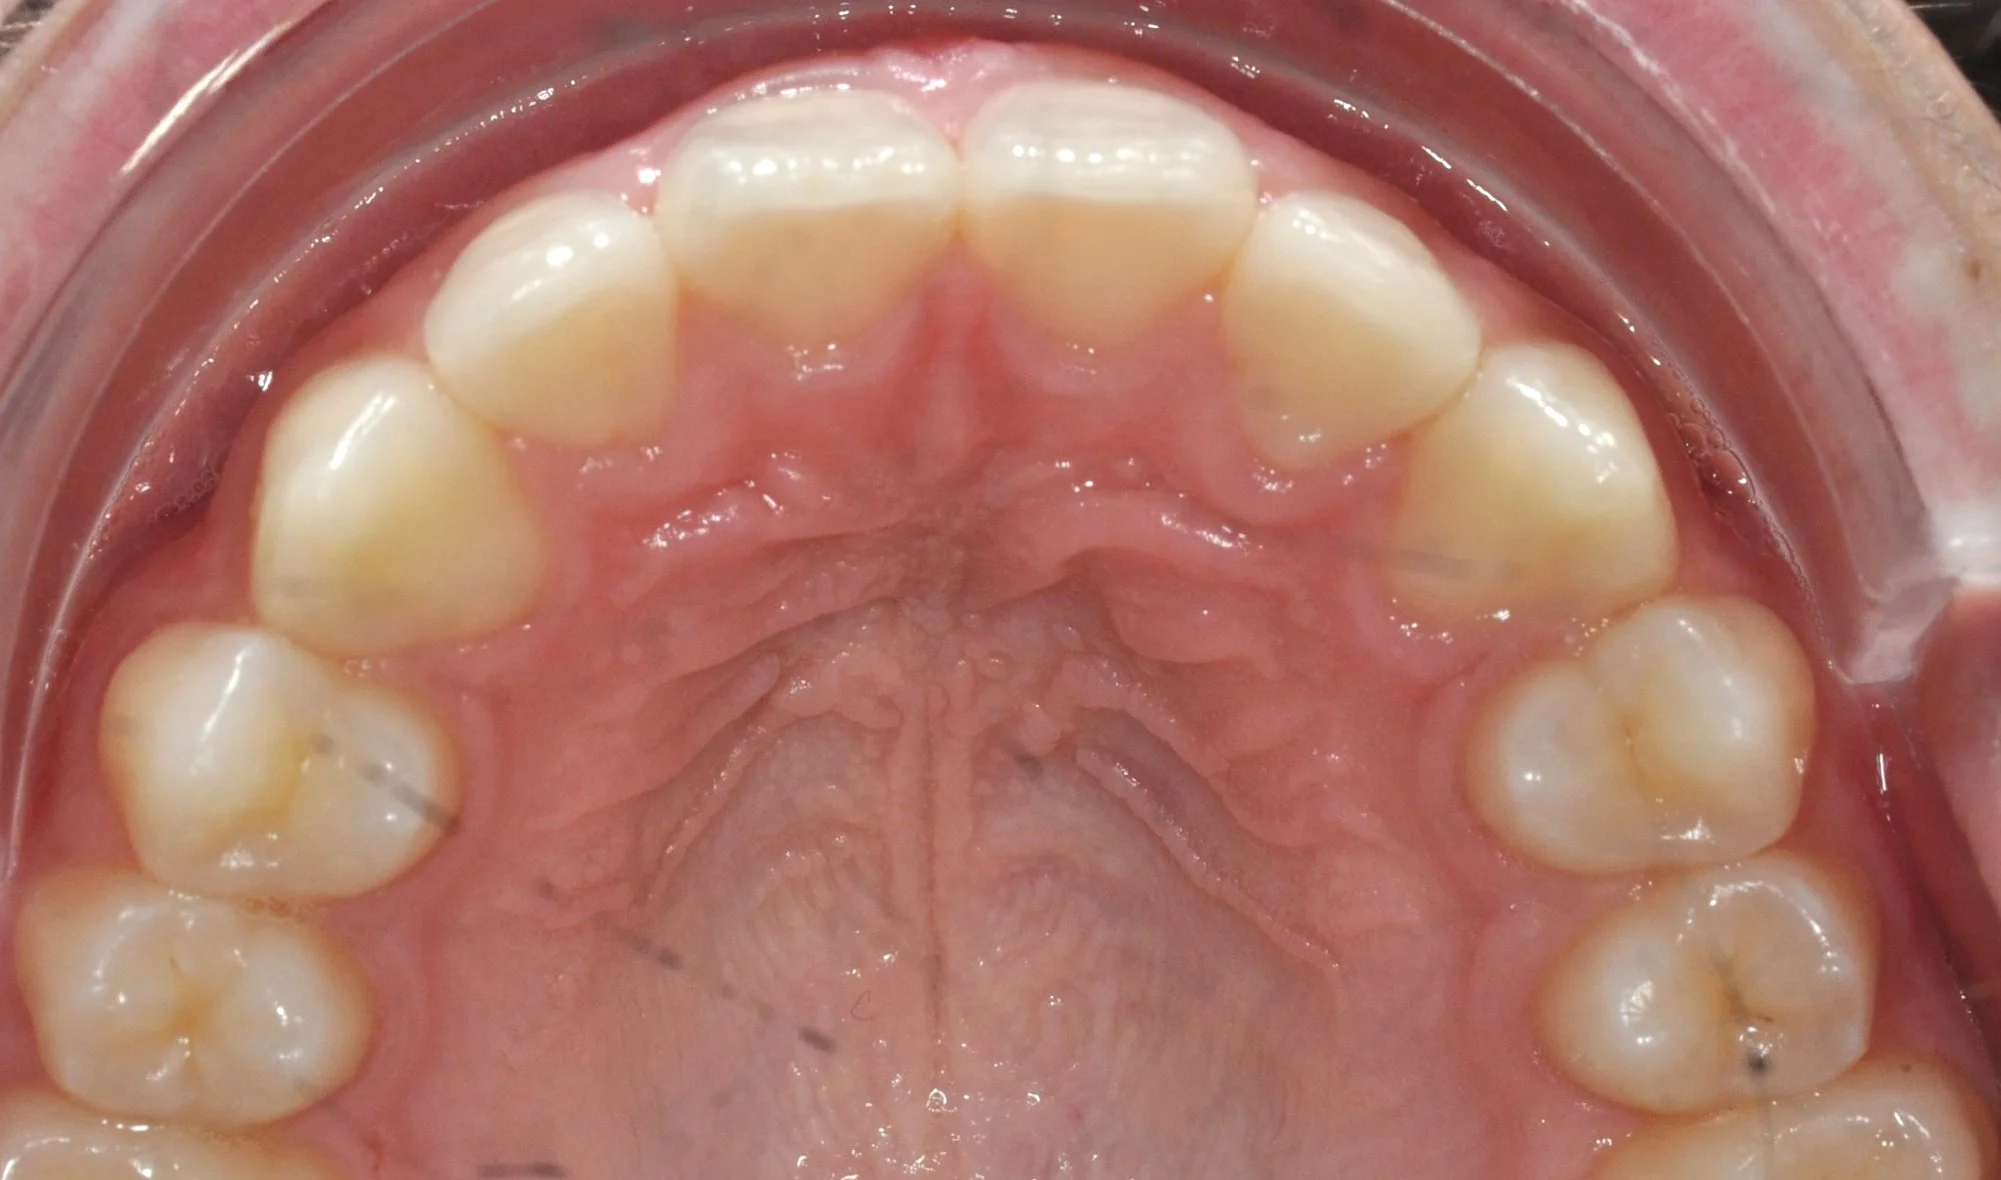

Caso 2 – Allineatori trasparenti in paziente adulto

Paziente adulto con importante affollamento dei denti inferiori, arcate strette e tendenza al morso aperto, con difficoltà nel corretto contatto tra i denti superiori e inferiori.

Il trattamento con allineatori trasparenti ha permesso, in circa 18–20 mesi, di riallineare i denti, ampliare le arcate e migliorare la chiusura del morso, ottenendo un risultato stabile, funzionale ed esteticamente armonioso.

PRIMA